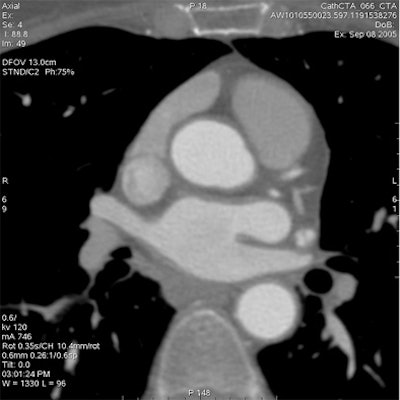

Which image would you rather be responsible for? Small 13-cm FOV (above) provides the best cardiac image quality at the lowest radiation dose compared with medium 25-cm FOV coronary CTA image (below). Thoracic image (bottom) maximizes anatomic coverage but at the cost of additional radiation and potentially more incidental findings. All images courtesy of Dr. Matthew Budoff.

The heart fits in a 25-cm field-of-view, permitting the use of a small bowtie filter in medium-sized and sometimes even larger patients, Budoff said. "We're only worried about the heart," he said.

For example, using protocol parameters of 600 mA, 120 kV, and a heart rate of 60 bpm, a small cardiac bowtie filter (standard 25-cm FOV) permits cardiac images to be acquired at dose-length product (DLP) of 474 (8.0 mSv), Budoff said. A medium bowtie filter (allowing reconstruction to 36-cm FOV) affords a dose of 791.4 DLP (13.4 mSv).

"What I call a cardiac CT always includes the great vessels, the myocardium, the left and right atrium, and pericardium," Budoff said. "I'm never only interested in the coronary anatomy. But in cardiac CT, I'm never interested in the lung. If I'm interested in the lungs, I can do a dedicated lung scan for an additional 0.7 mSv of radiation and have it interpreted separately and done properly."